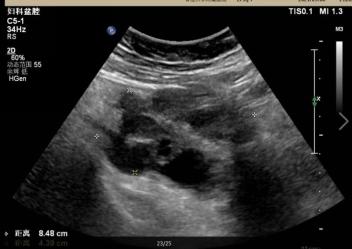

妇科超声(图1):右附件区见8.5x5.0x4.4cm囊性包块,壁厚,欠光滑,呈迂曲管状,内透声欠佳,见细密点状回声,囊壁见点条状血流信号;左附件区见6.7x5.4x4.8cm囊性包块,壁厚,欠光滑,局部呈迂曲管状,内透声欠佳,见细密点状回声,囊壁见点条状血流信号,内见少许卵巢组织,与卵巢分界不清;子宫前方见深约3.3cm液性回声,均透声可。超声提示:输卵管卵巢炎、输卵管积脓可能,盆腔积液。

妇科超声提示:输卵管卵巢炎、输卵管积脓可能,盆腔积液。